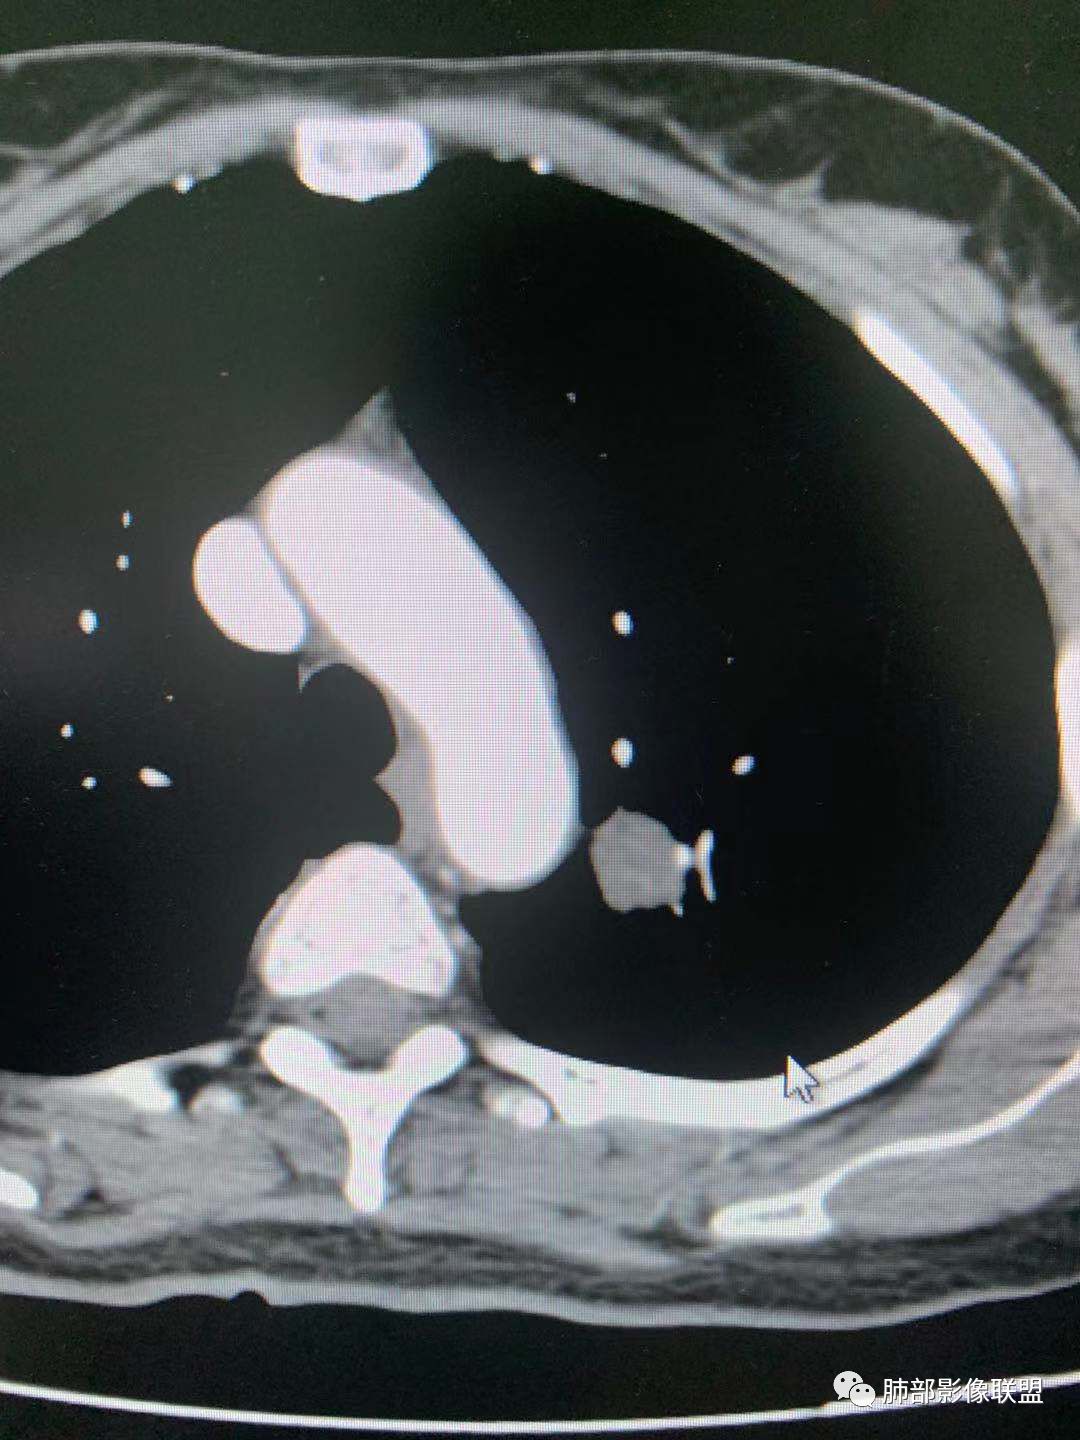

左肺上叶实性结节,光滑,支气管血管贴边,晕,强化持续。两年前就有,考虑psp。另外左肺上叶纵膈侧胸膜下及中带两处混合磨玻璃结节,考虑原位和微浸润可能,需要随访看看。

左肺上叶实性结节,边缘光滑清晰,血管贴边,渐进性延迟强化,密度均匀,考虑PSP.

贴边血管征,强化延迟,考虑PSP

左肺上叶实性结节,边缘光滑清晰,血管贴边,渐进性延迟强化,密度均匀,考虑PSP.但是强化幅度不够,需要鉴别早期肺癌 医学百科网 | YxBaike.Com

最大的靠后,有血管贴边征,渐进性明显强化,考虑PSP可能大

首先考虑PSP,周围可疑磨玻璃,鉴别恶性病变 医学百科网 | YxBaike.Com

中年女性,左肺上叶实性圆形结节,边缘有晕,血管及支气管贴边,强化尚均匀,渐进性明显强化,考虑为PSP可能